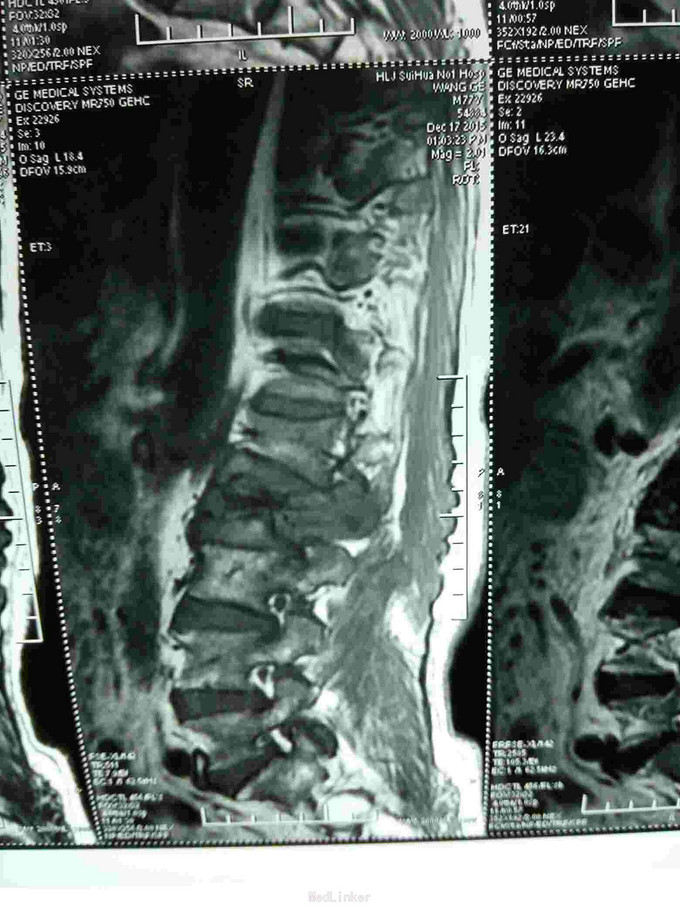

患者老年男性,77岁。因:腰痛,伴双下肢放射痛。活动受限二天。来诊。病人近半年间断腰痛,休息减轻。劳累加重。近二日腰背部疼痛明显加重。不能平卧于床。行走困难。双下肢放射痛。急来诊。因不能平卧,无法查核磁共振,门诊以:腰间盘突出收入院。

查体:神志清,语言流利。呼吸平稳。腹软,腰背部外形较好,无畸形。不能平卧,屈伸活动受限。床上取侧身蜷腿弯腰卧位。双侧下肢放射痛。肌力减退。皮肤感觉麻木。无辅助检查。

根据病史查体诊断:腰间盘突出症待确诊。应用消肿营养神经镇痛治疗。一天。查核磁共振示:腰椎多节段间盘突出伴椎管狭窄。第二腰椎骨破坏侵及椎板。部分突入椎管,脊髓受压。诊断:腰间盘突出伴椎管狭窄。第二腰椎转移癌,脊髓受压。经与家属沟通,查双肺CT:双肺下叶炎症。肺部纤维化。可见肿瘤阴影。肋骨及胸膜受累。胸椎部分骨破坏。最终诊断:双肺癌,胸椎,腰椎骨转移,脊髓受压。多节段腰椎间盘突出。病人至肿瘤科治疗。